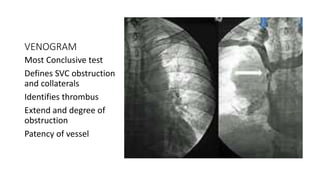

VENOGRAM

Most Conclusive test

Defines SVC obstruction

and collaterals

Identifies thrombus

Extend and degree of

obstruction

Patency of vessel